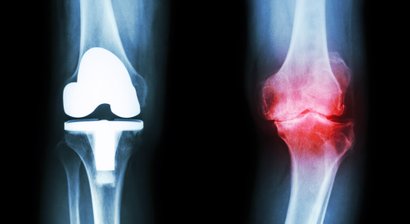

Bei Ihrem Besuch werden Sie von mir ausführlich über sämtliche moderne Therapie-und Operationsverfahren bei Sportverletzungen (z.B. Kreuzbandriss, Meniskusriss, Bandverletzungen, Patellaluxation), Abnutzungen (Knorpelschaden, Arthrose) und Fehlstellungen beraten.

Mein fachärztlicher Schwerpunkt liegt in der Behandlung des Kniegelenks. Durch die internationale Ausbildung an einer Knieklinik, aktive Mitgliedschaft in zahlreichen wissenschaftlichen Fachgesellschaften sowie langjährige Erfahrung führe ich auch komplexe Knieoperationen (u.a. Meniskustransplantation) und Kombinationseingriffe in höchster Fallzahl in Wien durch.